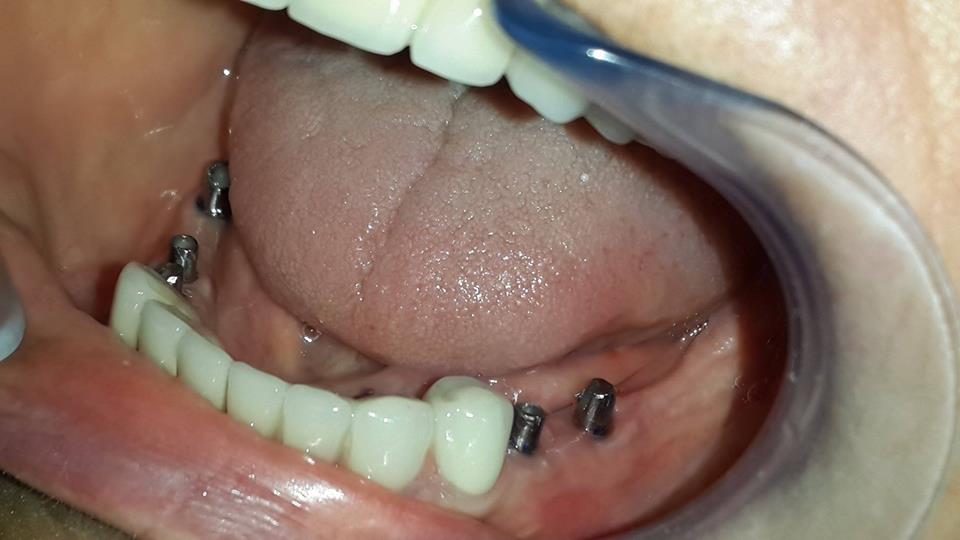

An example of complete rehabilitation of the oral cavity. Treatment included the removal of the old prosthesis, treatment of paradontitis, removal of a large cyst, implantation, clasp prosthesis.